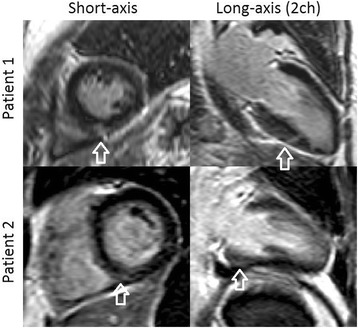

The degree of fibrosis was visually graded in LGE images by an experienced investigator (HE) (Fig. 2).

Fig. 2.

Typical example of right ventricular insertion point fibrosis marked with arrows in two patients with systemic sclerosis (SSc)

Fibrosis by late gadolinium enhancement

Late gadolinium enhancement (LGE) images were not obtained in three SSc patients because of inability to withstand further scanning due to discomfort. Three out of the nineteen SSc patients examined with LGE had septal fibrosis in the right ventricular insertion points. None of these patients had signs of previous myocardial infarction.

We found fibrosis in the right ventricle insertion points in three out of the nineteen investigated patients. We believe that this fibrosis is more likely a result of mechanical stress from a pre-clinical hypertensive pulmonary circulation, than an effect of local microvascular dysfunction since the MP at stress was at level with the other patients within the SSc group (stress MP = 3.6, 3.8 and 2.5 ml/min/g). To find out if microvascular function might be the cause of fibrosis in the insertion points, the study design would require the demonstration of localized hypoperfusion in the insertions points before the appearance of fibrosis.